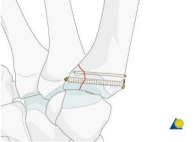

- Nắn kín và cố định trong: gãy di lệch có thể nắn được

Thực hiện nắn kín bằng cách kết hợp: Kéo theo trục dọc → Sấp đốt bàn → Ép vào nền đốt bàn ngón 1 [2]

Kiểm tra lại sự phục hồi mặt khớp dựa vào C-arm (màn hình tăng sáng)

Có 3 phương án cố định trong:

Xuyên qua nền đốt bàn ngón 1 vào xương thang.

Xuyên qua nền đốt bàn ngón 1 vào xương bàn ngón 2. [2]

Kết hợp cả 2.